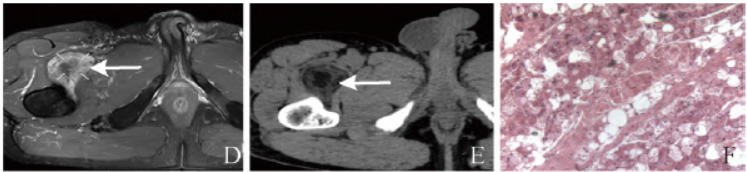

男,57岁,主诉:4个月前查体发现右侧髂腰肌及邻近肌间隙占位,无明显不适,肿物生长缓慢,呈逐渐增大趋势。体格检查:髋关节屈伸无明显受限,右侧髂腰肌下段内可触及一包块,无明显压痛,与周围组织界限清楚,浅表无静脉怒张,局部皮温不高,右下肢感觉肌力正常。MRI检查(图1A~D)提示脂肪肉瘤

可能。CT(图1E)提示含脂类肿瘤。

术中见右侧股骨上段前方肌间隙内肿物,大小约7.0 cm×5.5 cm×3.5 cm,表面呈灰红灰黄色,部分切面淡黄,部分切面灰黄;肿物周围附包膜,包膜完整,与周围组织界限不清。病理见图1F。免疫组化:S-100(+)、CD34(血管+)。最终诊断为冬眠瘤。

图1 男,57岁,右侧股骨上段肌间隙内冬眠瘤。轴位T1WI见右侧股骨上段前方肌间隙内团状高或稍低信号(箭,A),大小约7.7 cm×4.6 cm×4.7 cm,边界欠清,邻近肌肉软组织呈受压、移位改变,双侧股骨形态、信号未见明显异常;轴位T2WI脂肪抑制见病灶呈不均匀低信号(箭,B);冠状位T2WI见病灶信号呈类圆形(箭,C);增强扫描呈不均匀强化(箭,D);CT平扫

示右侧股骨前缘见团状脂肪密度影,其内密度不均,形态欠规整,CT值约为-8~61 Hu(箭,E);显微镜下见圆形、多角形细胞团,部分胞质内见嗜酸性颗粒及小脂滴,细胞核小而居中(HE,×100,F)